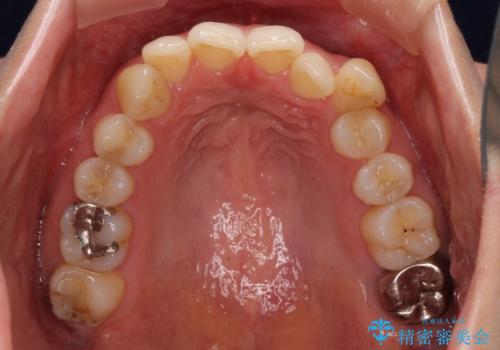

上下顎ともにIPR(歯と歯の間を削る)と歯列全体の拡大によって叢生が解消するように設計し、インビザラインにより治療を行うこととしました。